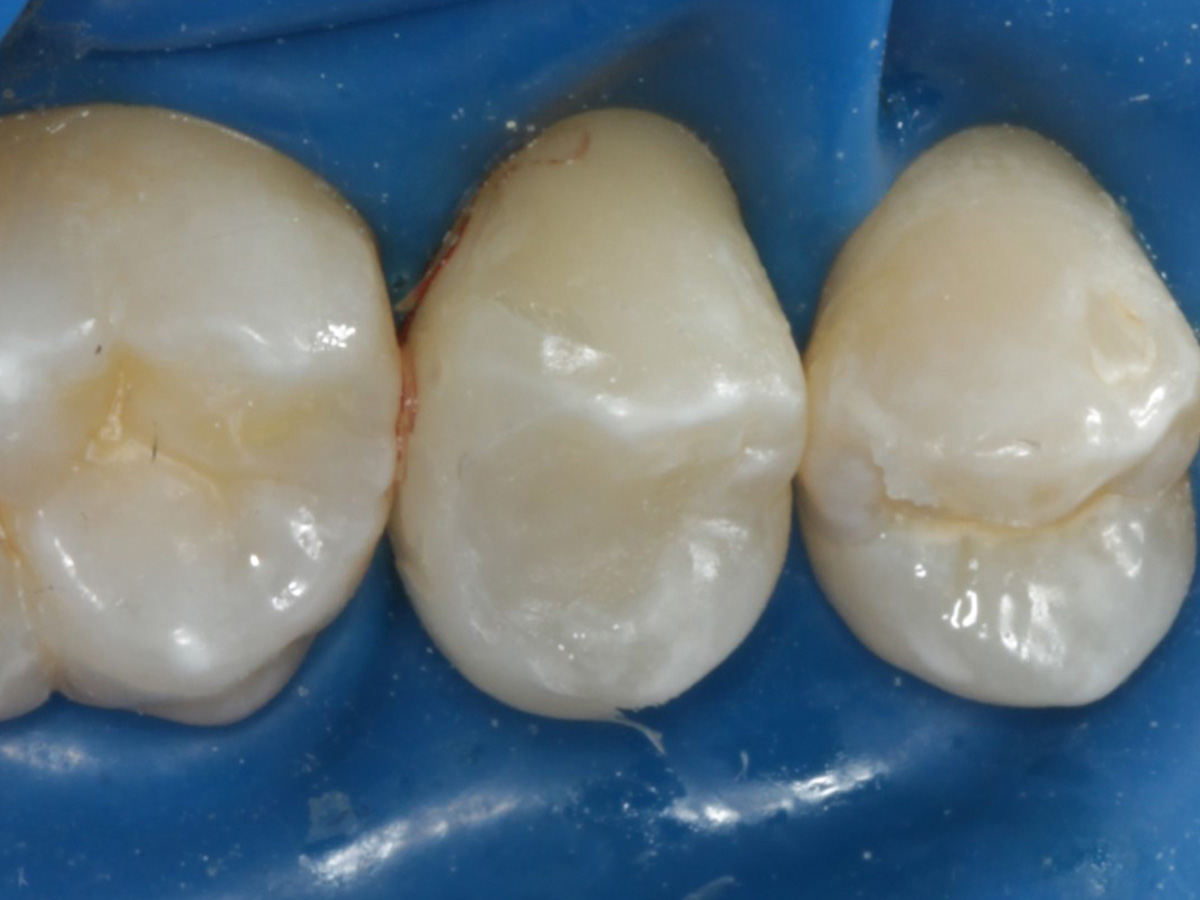

Abbildung 2

Intakte Kaufläche